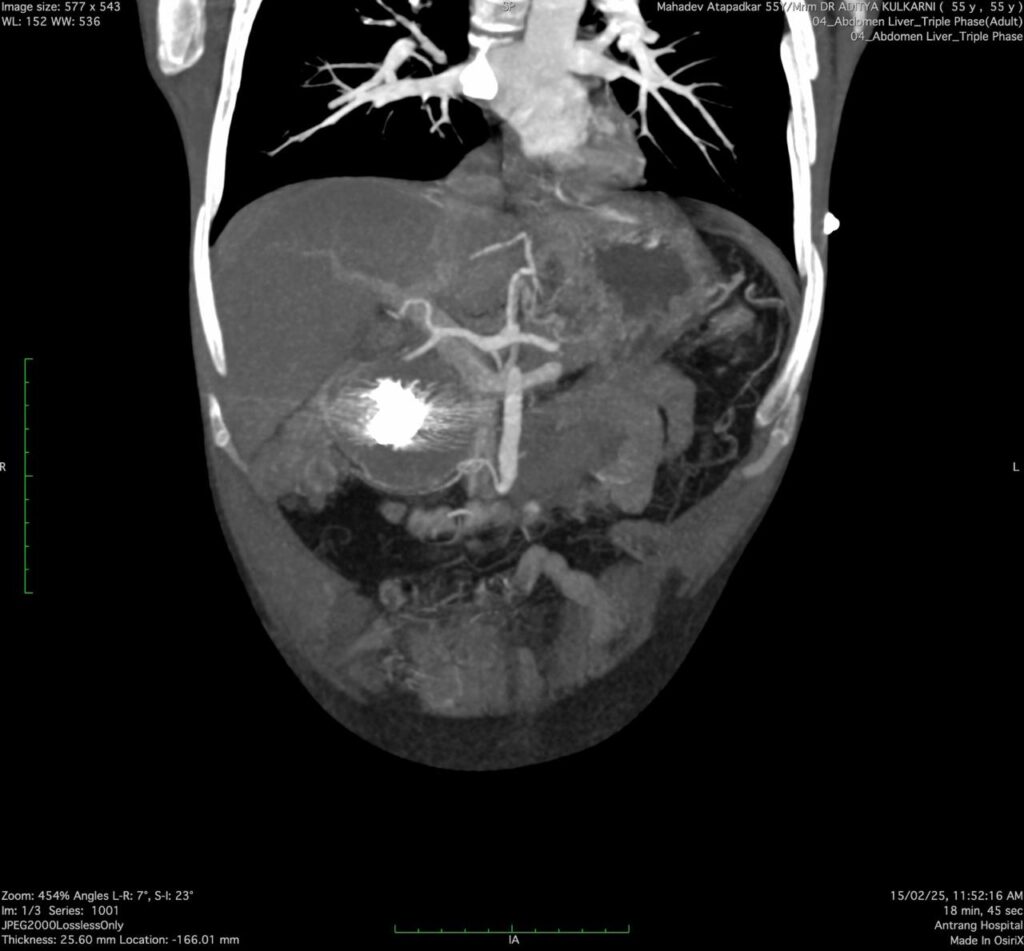

A 53 years- old male presented with a history of repeated GI bleeding for 20days. He had undergone UGI scopy and colonoscopy twice elsewhere with no obvious source of bleed. He was referred to us for further management Initial investigations revealed low haemoglobin levels (3.4), necessitating multiple blood transfusions. CECT abdomen done revealed 4.2×3.4cm pseudo aneurysm arising from Gastro duodenal artery branch within pseudocyst. There was bleeding within pseudocyst. Endoscopic ultrasound (EUS) guided coil +glue was performed to manage the pseudo aneurysm. Post procedure imaging showed Complete Occlusion of the pseudo aneurysm, and the patient was stabilized with supportive care, including IV fluids, antibiotics, and proton pump inhibitors (PPI)

Pseudo aneurysms in chronic pancreatitis are rare but can be fatal due to spontaneous rupture. The primary arteries involved are the splenic, gastroduodenal arteries. The diagnostic approach includes contrast- enhanced computed tomography (CECT), magnetic resonance angiography (MAR), and catheter angiography. Management options include endovascular interventions such as coil embolization or glue injection, surgical resection, or a combination of both as per the local expertise.